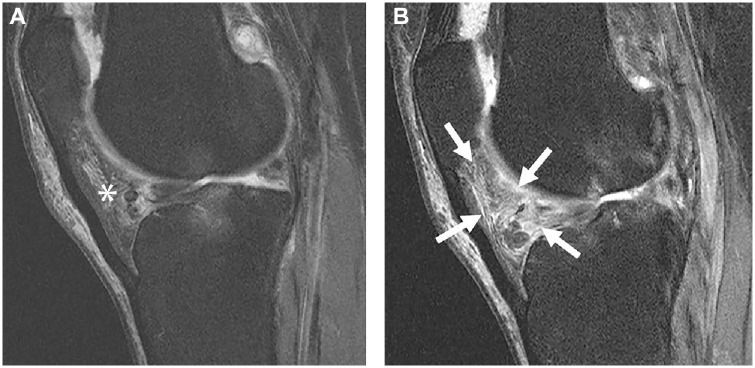

Abstract Image